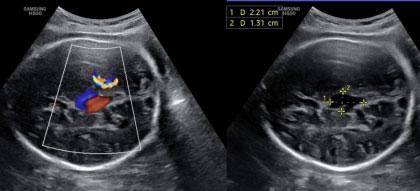

Fig 1 — A/C/O Close Fracture Supracondylar Humerus Left with Anterior Interosseous

CONCLUSION